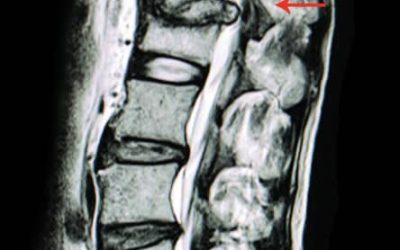

Mielopatía cervical: causas, síntomas y tratamiento

La mielopatía cervical es un trastorno que afecta la médula espinal en el cuello, común en personas mayores pero no exclusivo de ellas. Resulta de la compresión medular y provoca síntomas neurológicos variados. Entre las causas, se encuentran degeneraciones por edad, hernias de disco y traumatismos, todos afectando significativamente la calidad de vida. Un diagnóstico y tratamiento oportunos son fundamentales para mejorar el pronóstico y el bienestar del paciente.